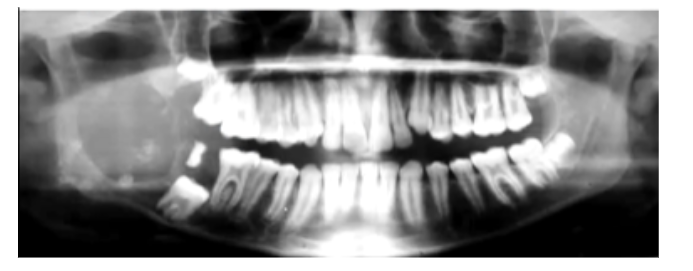

Where do Ameloblastomas commonly affect?

80% are found in the Mandible, most at the angle (but can occur anywhere in jaws)

More aggressive in maxilla

Once it exits bone and enters soft tissues - easier expansile growth - harder to treat

Why do Ameloblastomas more commonly affect the Angle of the Mandible?

Ameloblastoma arise from the Dental Lamina which is Epithelial in Origin.

Most Dental Lamina is found at the angle of the mandible